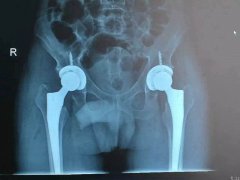

近日,我院骨科成功為一名老年男性患者實(shí)施雙側股骨頭無(wú)菌性壞死人工髖關(guān)節小切口DA……